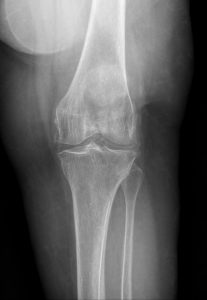

Fig. 1 AP view of the knee.

Fig. 2 Annotated image showing marginal osteophytes and meniscal chondrocalcinosis, consistent with CPPD.

Calcium pyrophosphate deposition disease (CPPD) involving the knee, characterized by chondrocalcinosis within the menisci and articular cartilage. CPPD results in calcium pyrophosphate crystal deposition that promotes cartilage degeneration and secondary osteoarthritic changes, including marginal osteophyte formation and joint space degeneration.